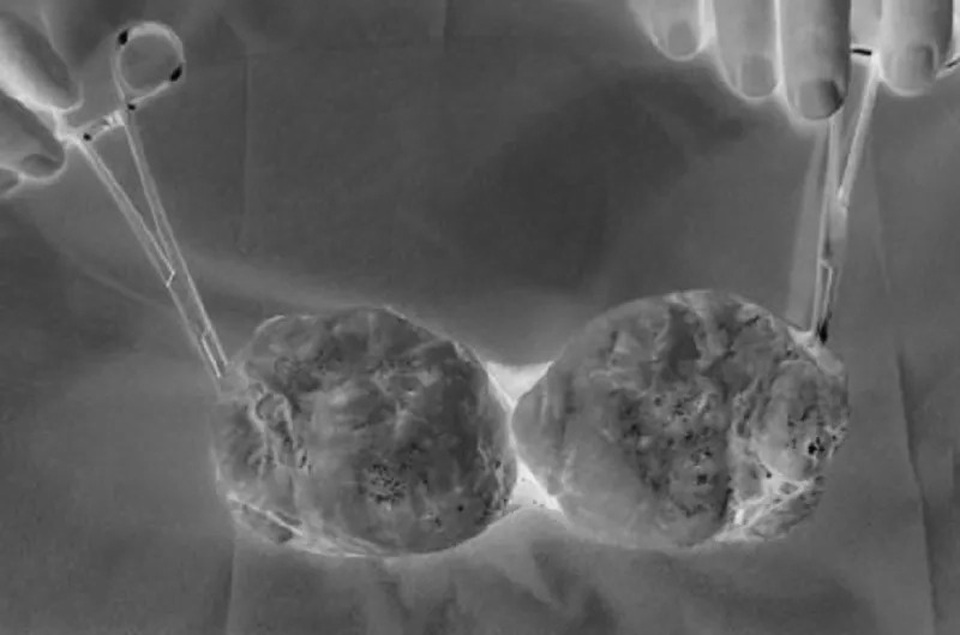

Một trường hợp bị ung thư tinh hoàn phải phẫu thuật cắt bỏ tại Bệnh viện Bình Dân

Phẫu thuật là phương pháp điều trị ung thư tinh hoàn